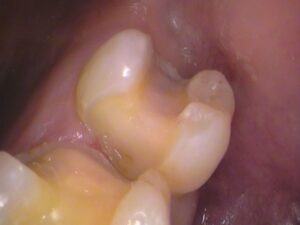

5番目の歯のレジンを取り除きました。

う蝕検知液という、虫歯を染色するお薬を塗って、虫歯をチェックします。

5番目の歯です。

赤く色が染まっている箇所が虫歯です(*_*)

やはりレジンの内部に虫歯が広がっていました。

赤い箇所の虫歯を削っていきます。

虫歯をしっかりと取ったところです。

虫歯の取り残しの無いように染色されないところまで、きれいに取ります。